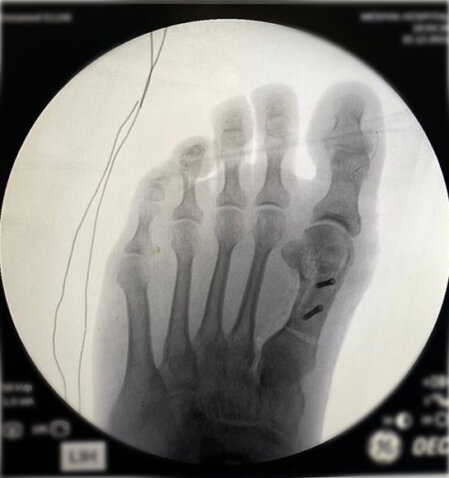

Halluk valgus ayak baş parmağının zaman içerisinde değişik nedenlerle eğilmesi ile ayak yan tarafında çıkıntının da eşlik ettiği bir rahatsızlıktır. Sıklıkla bayanlarda görülmesine rağmen erkeklerde ve çocukluk yaşlarında da karşılaşılmaktadır. Ayağın yan tarafında olan çıktı ve baş parmağın diğer parmakları itmesi ile ayakta şekil bozukluğu ve ağrı oluşur. Bu şekil bozukluğu kişinin ayakkabı giymesinde sıkıntılara neden olabilir.

Tedavisinde ayağın yük veriri pozisyonda çekilen grafileri üzerinde yapılan ölçümlerden sonra hastanın yaşı ve aktivite seviyesine göre kişiye özel planlanmaktadır. Erken dönemlerde ayakkabı modifikasyonu, parmak arası makarası ve gece ateli kullanılmaktadır. Cerrahi gerekliliğe hastanın deformitesinin büyüklüğüne ve hastanın taleplerine göre karar verilmektedir.

Aşağıdaki grafiyi öncesi sonrası şeklinde görmek için farenizi sağ sola hareket ettiriniz.

Yukarıdaki grafileri daha net ve büyük görmek için üzerine tıklayabilir. Sağ üst köşedeki + - tuşları ile daha da büyütebilirsiniz.